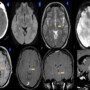

23 year old lady with tingling numbness in the right upper limb

No focal deficits

No significant past history

No neurological deficits on examination

MRI BRAIN (P+C) done for further evaluation

DIAGNOSIS: Capillary telangiectasias

•Mostly located in the brainstem (most commonly in the pons) (1)

•Often solitary and rarely can be multiple (1)

•Usually not seen on CT or catheter angiography (DSA)

•T1 may be iso to hypo and subtle bright on T2/FLAIR

•T2*GRE /SWI: Shows low signal intensity due to deoxyhemoglobin from sluggish flow and not due to bleed or mineralisation (2)

•Post contrast T1WI, may demonstrate stippled enhancement

•If large, can show branching/linear draining veins (3)

•No touch lesion & no follow-up is required if the imaging appearances are characteristic